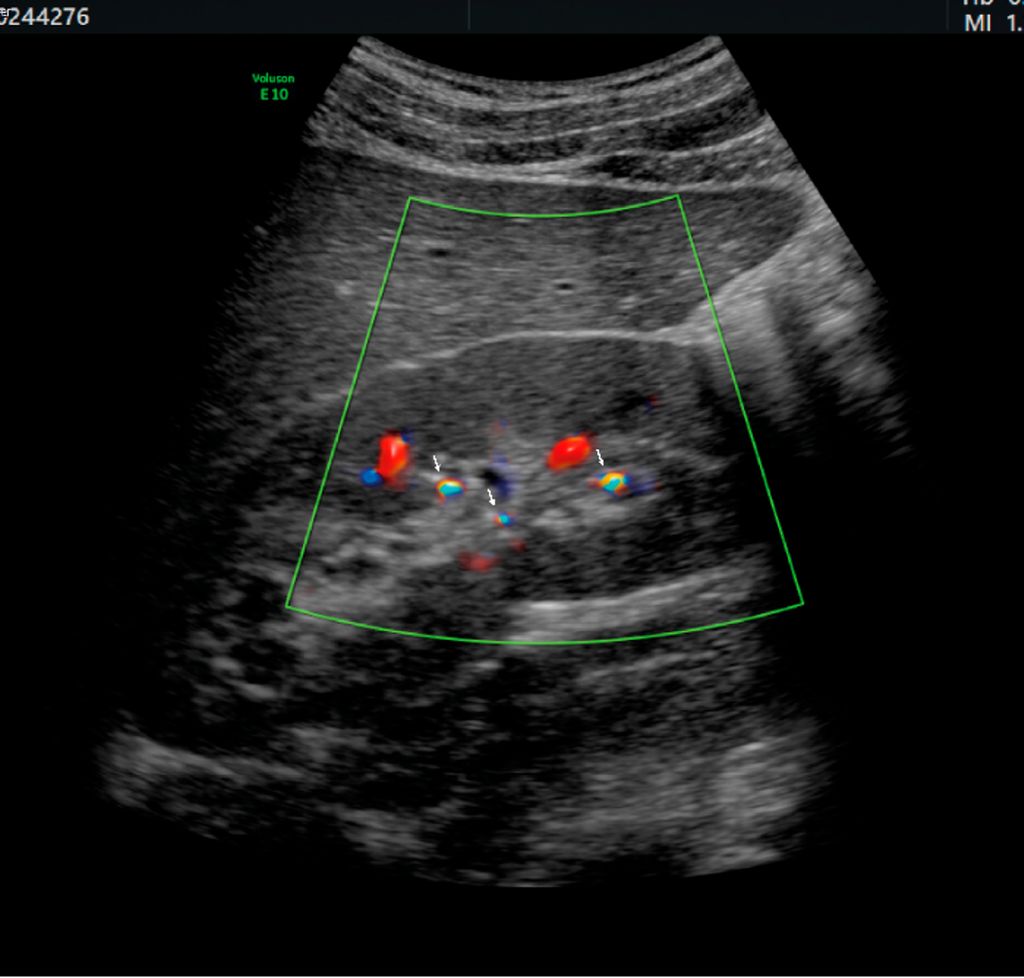

Abb. 3: Rechte Niere eines 16-Jährigen mit Zystinurie. Nach flexiURS am Vortag sieht man kleinste Residualkonkremente nur mithilfe des bunten Twinkling-Artefakts im Doppler. Tricks für gutes Twinkling: niederfrequenter Schallkopf, niedrige Dopplerfrequenz. Und: PRF (Puls-Repetitions-Frequenz) hochdrehen, um das bunte „aliasing“ der Blutgefäße zu beseitigen

Das Gute ist: Ultraschall ist bei Kindern sehr aussagekräftig. Und die Nutzung des Twinkling-Artefakts im Doppler ermöglicht auch die Detektion kleinster Körnchen (Abb. 3). Je kleiner und schlanker das Kind und je hartnäckiger der Untersucher, desto besser lässt sich auch ein Harnleiterstein darstellen. Die Beurteilung der Röntgendichte ist nicht so wichtig, denn – nicht schattengebende – Harnsäuresteine kommen bei Kindern praktisch nicht vor und folglich gibt es die Option der Litholyse nicht. Ob eine Stoßwellentherapie (ESWL) aussichtsreich ist, entscheidet sich nicht anhand der Houndsfield-Units (HU) im CT,sondern anhand der Steinlast im Ultraschall sowie des Zystin/Krea-Quotienten im Harn (Zystinsteine lassen sich trotz niedriger HU schlecht(-er) desintegrieren).9